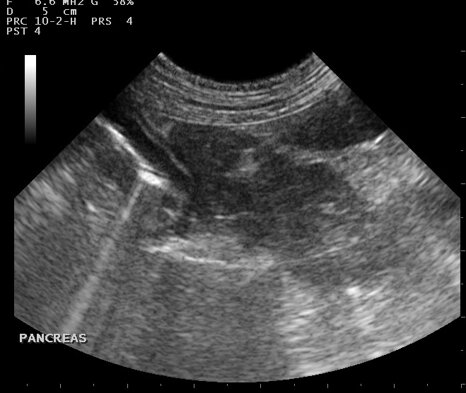

L’esame ecografico permette un’indagine non invasiva degli organi interni (fegato, pancreas, utero, intestino, reni...), è un esame indolore che, tranne in casi particolari, richiede solo una delicata contenzione e non necessita di sedazione. Spesso affianca e completa l'esame radiografico nella formulazione della diagnosi. L'ecografia può essere utilizzata anche per gli animali esotici e si rivela determinante nella diagnosi delle patologie cardiache.

Il centro dispone di una strumentazione ecografica di ultima generazione. Eseguiamo in sede esami ecografici ed ecocardiografici, anche su appuntamento.